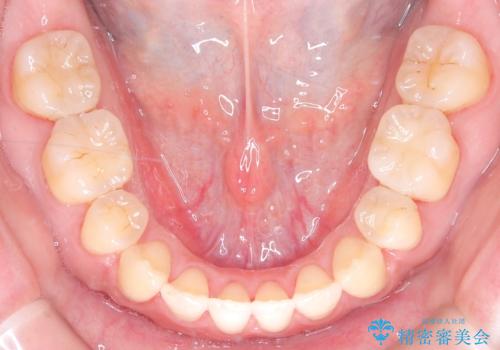

- 前歯のガタガタや八重歯の位置の乱れが気になっていた患者様に対して、ワイヤー矯正を行いました。矯正の過程で、スペースを確保するために上下左右の小臼歯を抜歯し、歯全体のバランスと機能性を考慮しながら理想的な歯列に仕上げました。

治療後は、前歯の位置や噛み合わせが整い、見た目も機能面も大きく改善されました。きれいな歯並びを得ることができ、患者様にも非常に満足していただけました。

抜歯によって確保したスペースを活用し、効率的に歯列を整えました。前歯のガタガタと八重歯が解消され、自然で美しい仕上がりを実現しました。